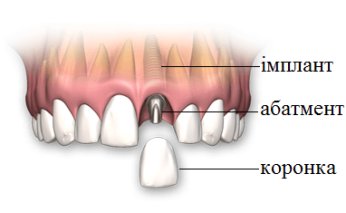

Імплантація - це метод вживлення імплантату (штучного кореня) у верхню або нижню щелепу.Такий штучний корінь виготовляється з спеціального сплаву, що надійно вживлюється в кістку та стає надійною опорою, на яку встановлюється коронка.

- кріплення абатменту та коронки;